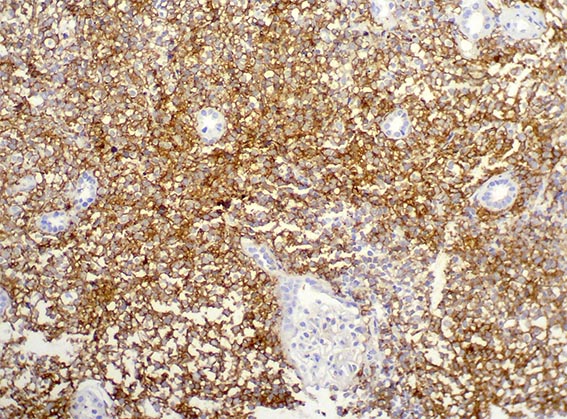

La inmunohistoquímica demostró positividad difusa para CD20 y CD10, con índice proliferativo del 80% (Ki67). Caso diagnosticado por la sección de Hematopatología de nuestro Departamento.

Figura 8. Inmunohistoquímica para CD10, X400.